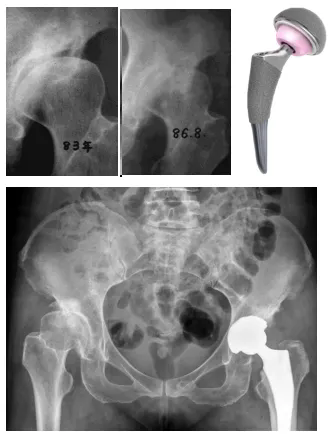

圖3-4:術前影像(右側髖關節發育不良)

圖7:術后影像(髖臼對股骨頭的包容良好)

(正常髖關節X線(左圖)顯示髖臼對股骨頭的包容良好;發育不良髖關節X線(右圖)顯示髖臼對股骨頭的包容不足。)

(35歲患者診斷DDH后未及時矯正,3年發展為髖骨關節炎行全髖關節置換術)